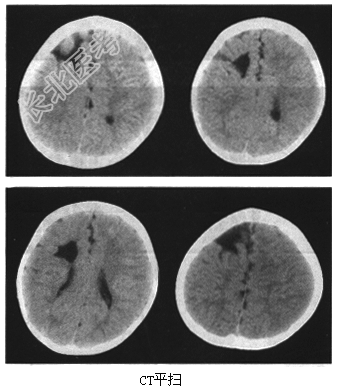

- [材料题] 患者,女,8岁。因为癫痫、智力低下来院检查,影像学检查如下图。